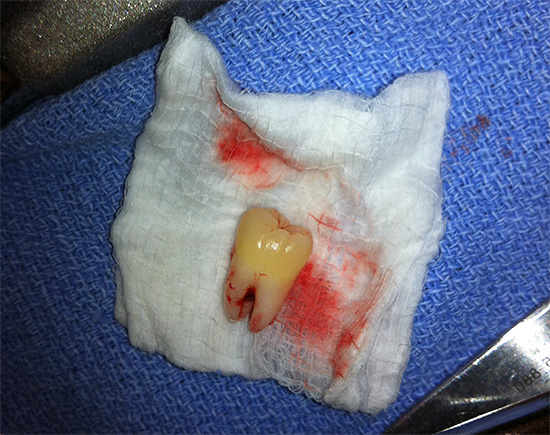

Foto dei denti del giudizio rimossi:

Nella foto - un dente del giudizio rimosso in alcune parti: